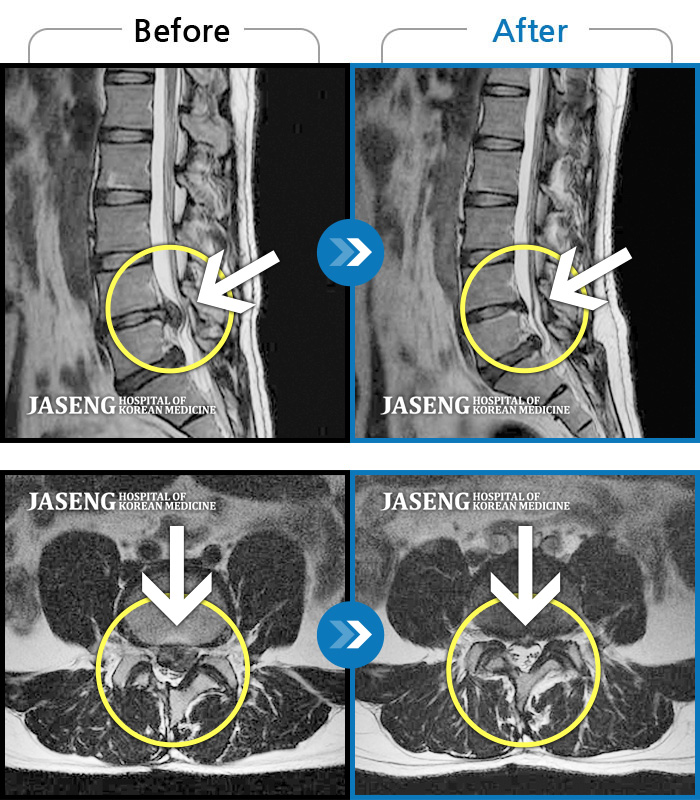

허리디스크

잠실 · 한상욱 원장

허리, 우측 엉치와 다리 후면 및 발끝까지 저림과 통증이 심하고 힘까지 빠진다.

촬영시기

2022.06.15 ~ 2022.11.11

2022.12.02